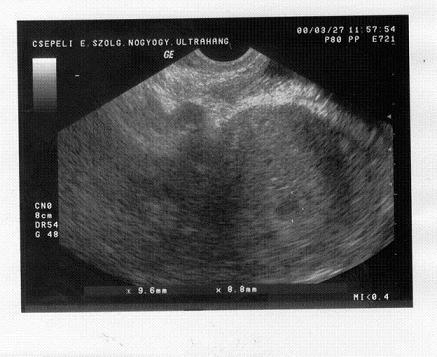

Sziasztok megjöttem.

Minden oké. szép szabályos 9mm-es petezsák. 5 hetes. Utrót írt fel és táppénz. Két hét múlva kontrol.

Látok feljebb egy fekete foltocskát is remélem hogy ................... vagy csak káprázat.

Én feljebb, de lejjebb is látok egy fekete pöttyöt! :lol: (3-as ikrek?? :lol: :lol: :lol: )

én is 2 foltot látok, de csak szóltak voltak, ha többes szám van :wink: Nekem 5 hetesen egyértelműen 2 petezsák látszott egy 7 és egy 5 mm-es, szóval ,ha több lenne, azt látta volna a doki, nyugi :wink: